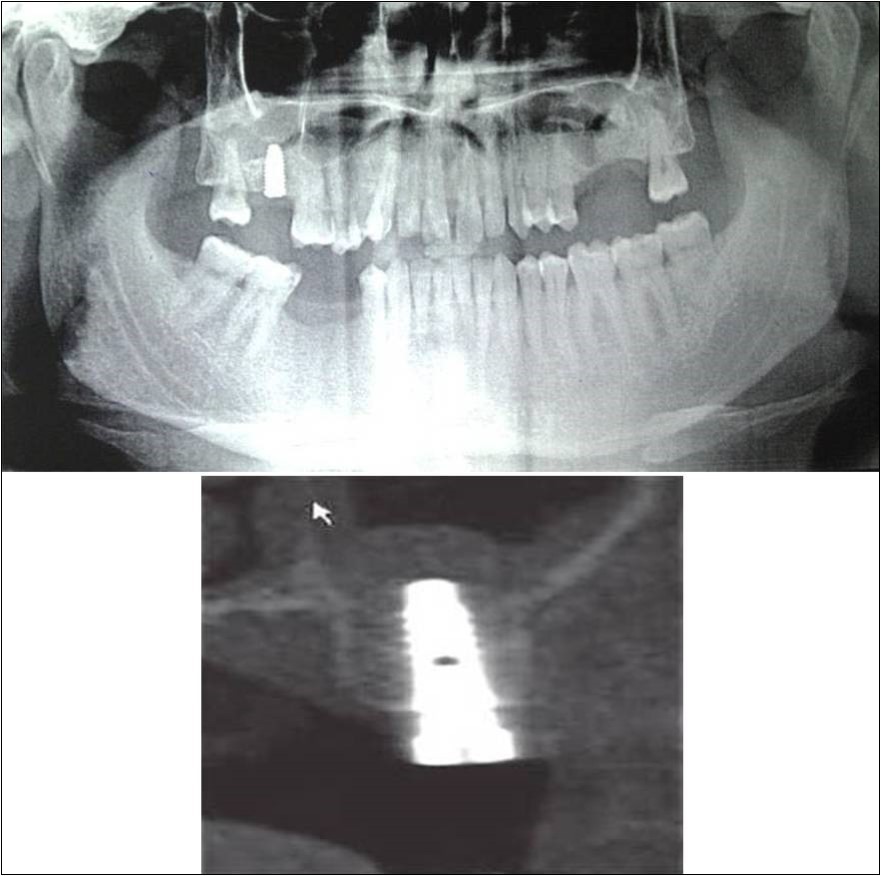

Figure 13.(a,b) Pre-treatment OPG and cross section of CBCT showing residual alveolar bone height for Case No.4;

Figure 14.(a,b) Post-treatment OPG and cross section of CBCT showing residual alveolar bone height for Case No.4;

Clinical and Radiological Assessment:

1.Partially edentulous maxillary arch with missing 16 and 26;

2.Increased pneumatisation of right and left maxillary sinus;

3.Height of available bone-

16 region: 6.5mm;

26 region: 6.2mm;

4.Transverse thickness of available bone (CBCT evaluation)-

16 region: 8.3mm;

26 region: 10.5mm;

5.Fixed orthodontic appliance;

6.Inter-ridge space adequate to place implant (11mm).

Treatment:

Patient underwent the procedure of indirect sinus elevation using sinus osteotomes in relation to 26 region. Calcium phosphosilicate putty was dispensed as the graft material through the crestal osteotomy site to maintain the elevated sinus membrane followed by placement of 5 x 10mm dental implant under local anaesthesia and strict aseptic protocols. The implant was allowed to osseo-integrate for a period of six months during which the patient was followed-up periodically and was assessed for peri-implantitis, crestal bone loss and mobility. Patient was taken-up for direct sinus elevation via lateral window approach for sinus augmentation i.r.t 16 region. Under aseptic conditions and local anaesthesia, lateral wall of maxilla was exposed after muco-periosteal flap elevation. A window was created of 1cm diameter corresponding to apical aspect of 16. Sinus membrane was identified and elevated using sinus elevators and reamers without perforating the lining. Once the sinus membrane was elevated, phosphosilicate putty was dispensed through the lateral osteotomy site as the graft material to achieve an augmentation of 1cm assessed clinically and confirmed using post-operative OPG. At the end of 6 months, a repeat CBCT scan was advised to evaluate the increase in bone height. (Figure 13a,b, pre-treatment; Figure 14a,b, post-treatment)